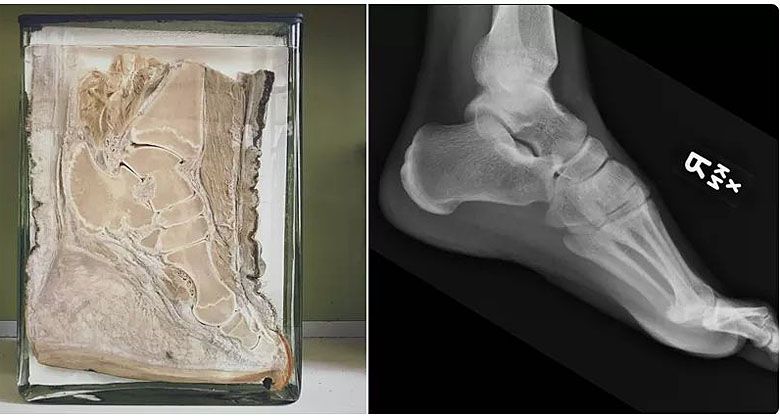

Stopa słoni w porównaniu z ludzką stopą